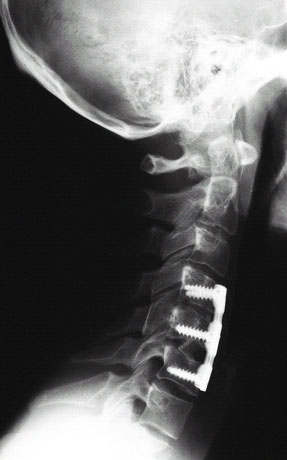

Abb. 3+4 von links

Zustand nach operativer Versorgung des Bruches mittels Titanplatte, welche mit 6 Schrauben in den 4.,5.und 6.Halswirbelkörper verankert sind. Die beiden Bandscheiben ober und unterhalb des gebrochenen Wirbelkörpers wurden entfernt und durch Eigenknochen aus dem Beckenkamm des Patienten ersetzt. (linkes Bild) Rechts das Röntgenbild nach ca. 8 Monaten, eine knöcherne Verrbindung zwischen den verschraubten Wirbelkörpern ist entstanden.